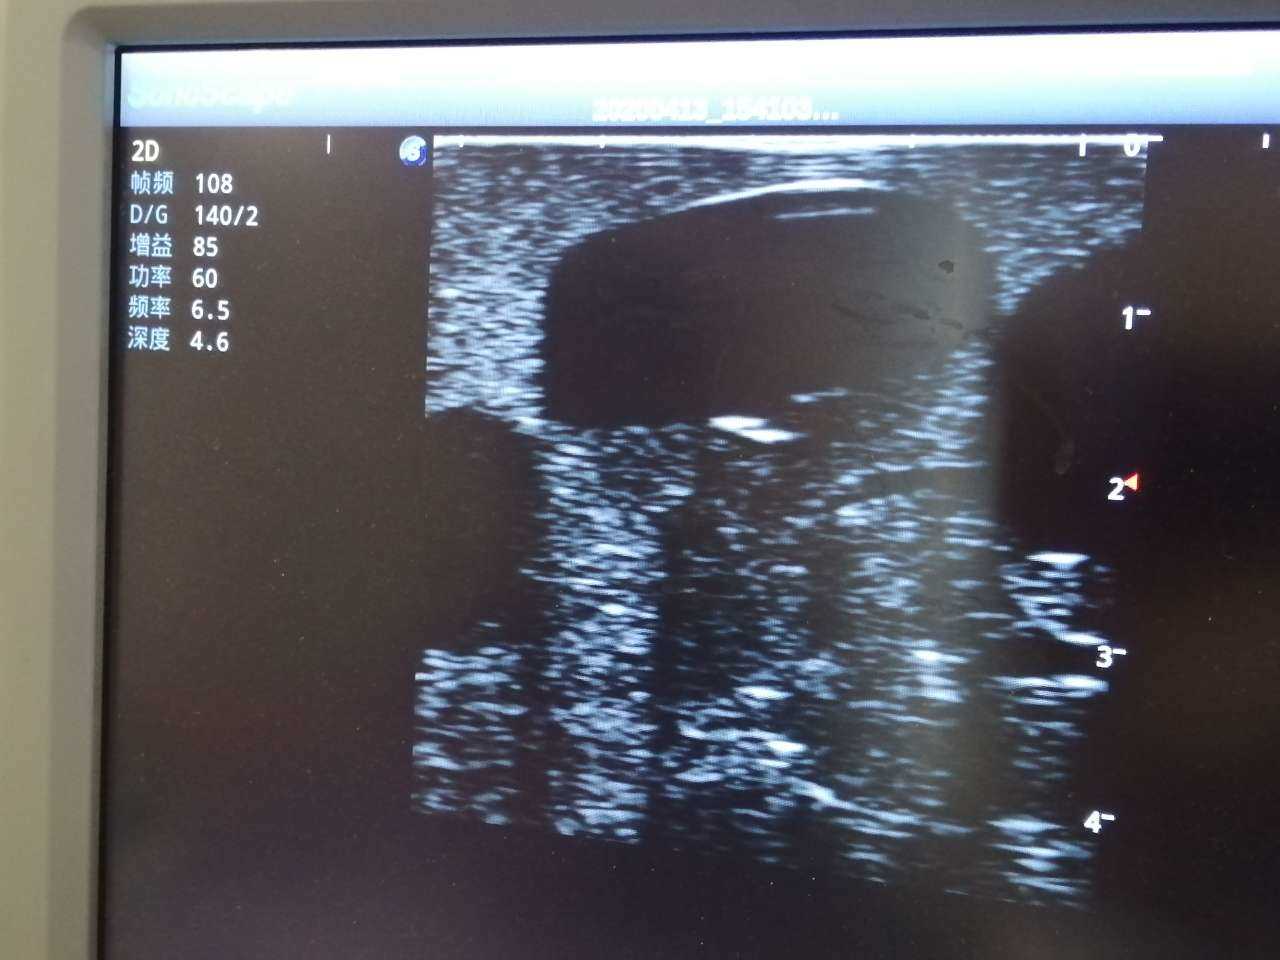

· High-quality ultrasound images to show skin, soft tissues, abscess cavity and pus

· Different abscess types: single sac on the right side and multiple sacs on the left side